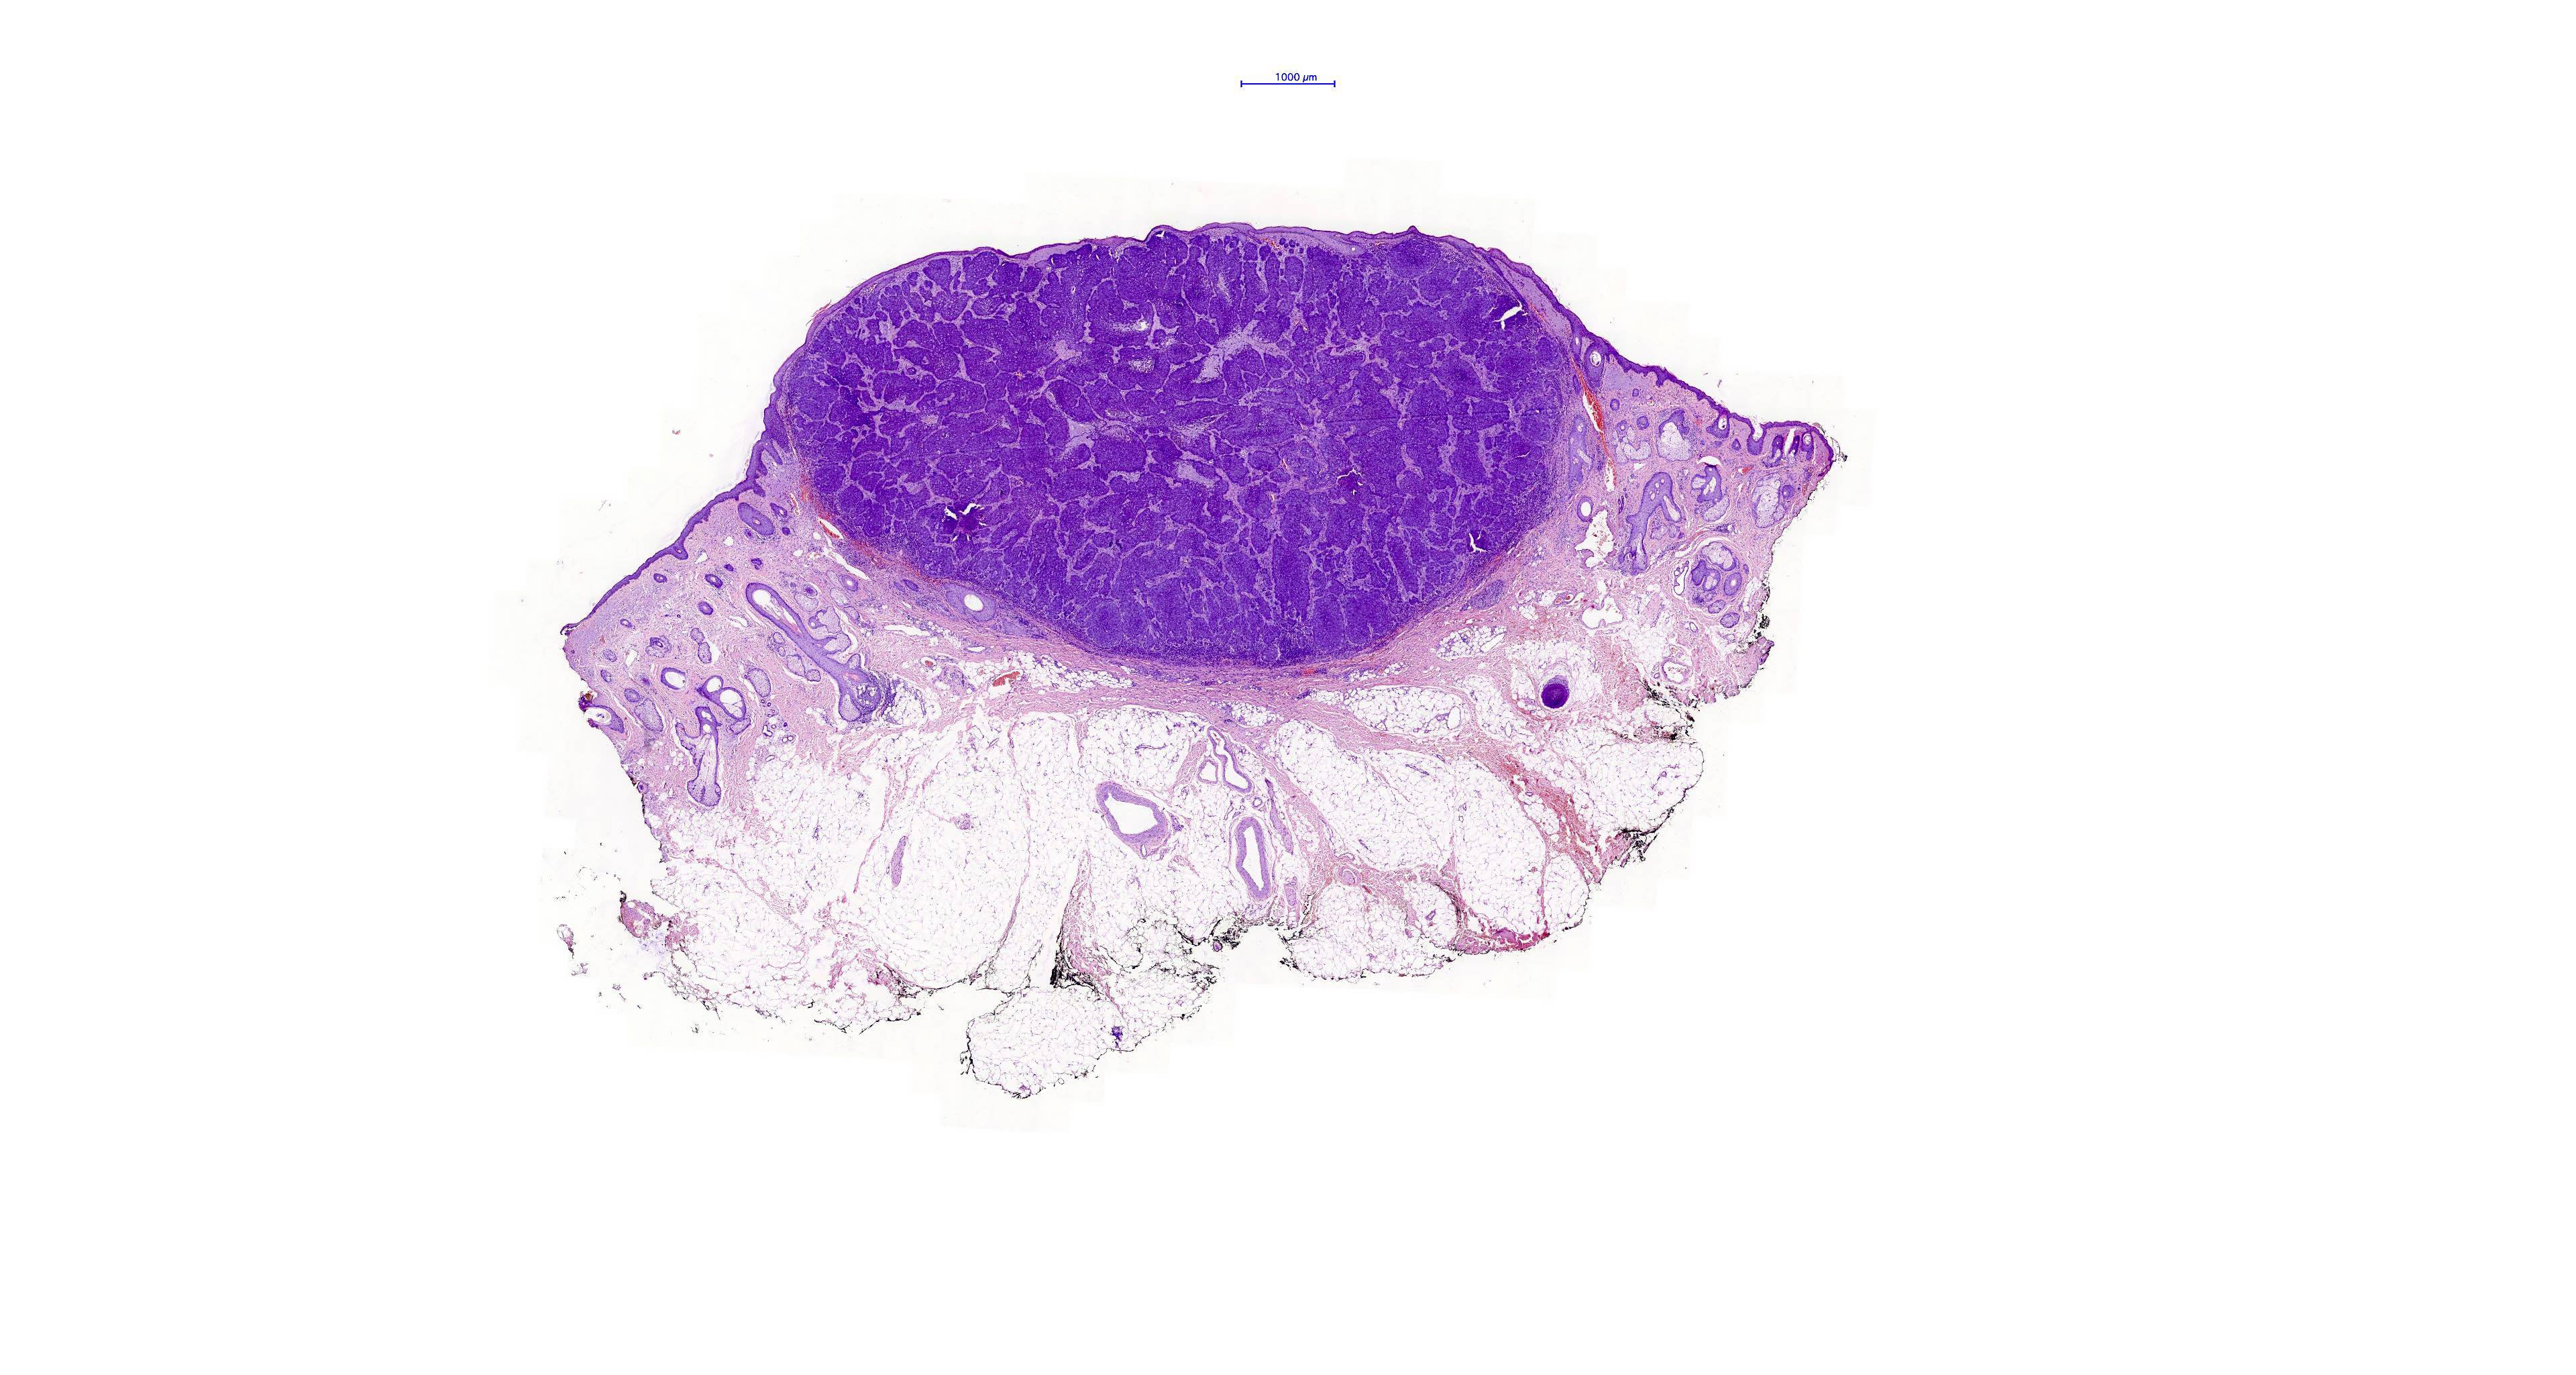

Common variants (Calonje: McKee's Pathology of the Skin, 5th Edition, 2019)

- Nodular and nodulocystic BCC

- Relatively circumscribed mass

- Epidermal or follicular attachment variably present

- Large basaloid lobules with peripheral nuclear palisade

- Lobules may be solid or show central cyst formation due to excessive mucin production

- Fibromyxoid stroma

- Cleft formation between tumor lobules and stroma

- Pleomorphism is generally mild

- Variable mitotic activity and apoptosis

- Sometimes necrosis en masse

Microscopic (histologic) images

Contributed by Antonina Kalmykova, M.D., Phillip H. McKee, M.D., Sate Hamza, M.D., Eduardo Calonje, M.D.,

Wayne Grayson, M.B.Ch.B., Ph.D., James Sampson, M.B.B.S., M.Sc. and Assia Bassarova, M.D., Ph.D.